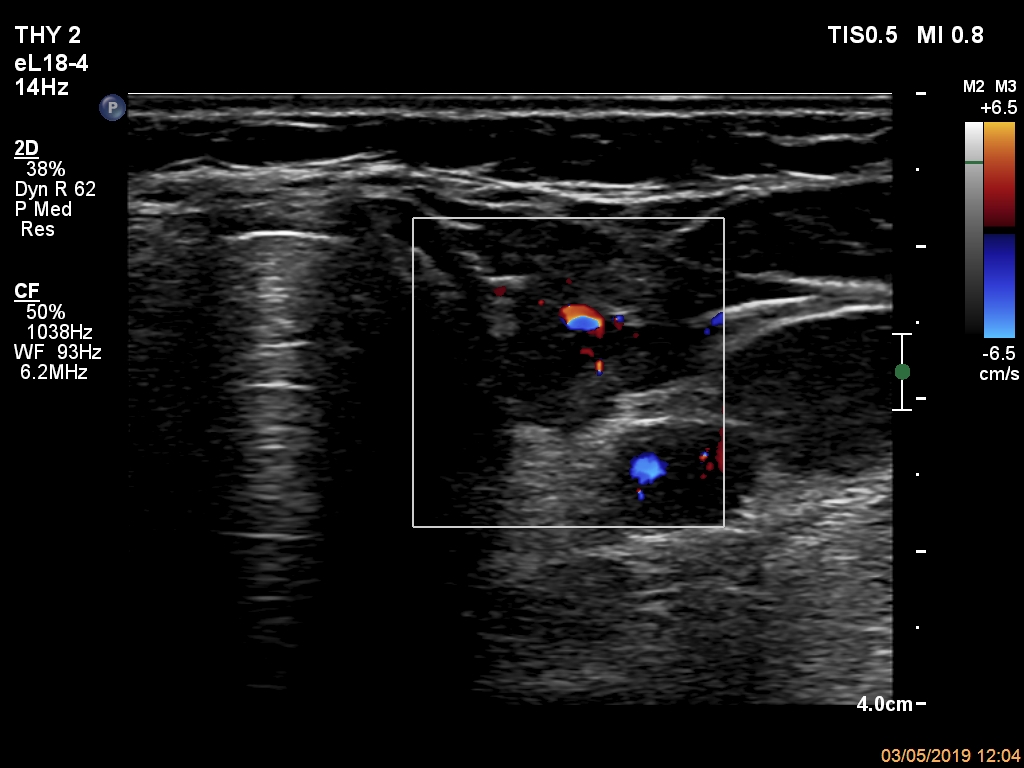

Right lobe, longitudinal scan

Left lobe, transverse scan, color Doppler mode. The vascularization is not sepcific.